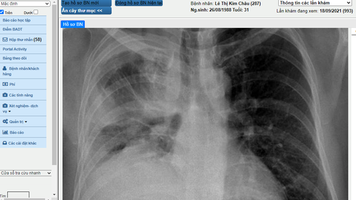

🩻 Phát triển kỹ năng phân tích X quang ngực thẳng

X quang ngực thẳng đã trở thành một cận lâm sàng thường quy, sẵn có và cung cấp nhiều thông tin hữu ích. Không chỉ đánh giá được nhu mô phổi, hình ảnh x quang ngực thẳng có thể cung cấp thêm các thông tin về cấu trúc của tim – cung động mạch chủ - van tim, chất lượng đường dẫn khí, xương sườn – cột sống – xương đòn, các khớp và cả mô mềm vùng ngực…

🔍 Phân tích hình ảnh

Phân tích hình ảnh cùng giảng viên giúp phát triển kỹ năng hài hòa và bám thực tế

💻 Hệ thống PACS

Ứng dụng hệ thống PACS giúp học viên nhìn hình tốt hơn, học hiệu quả hơn